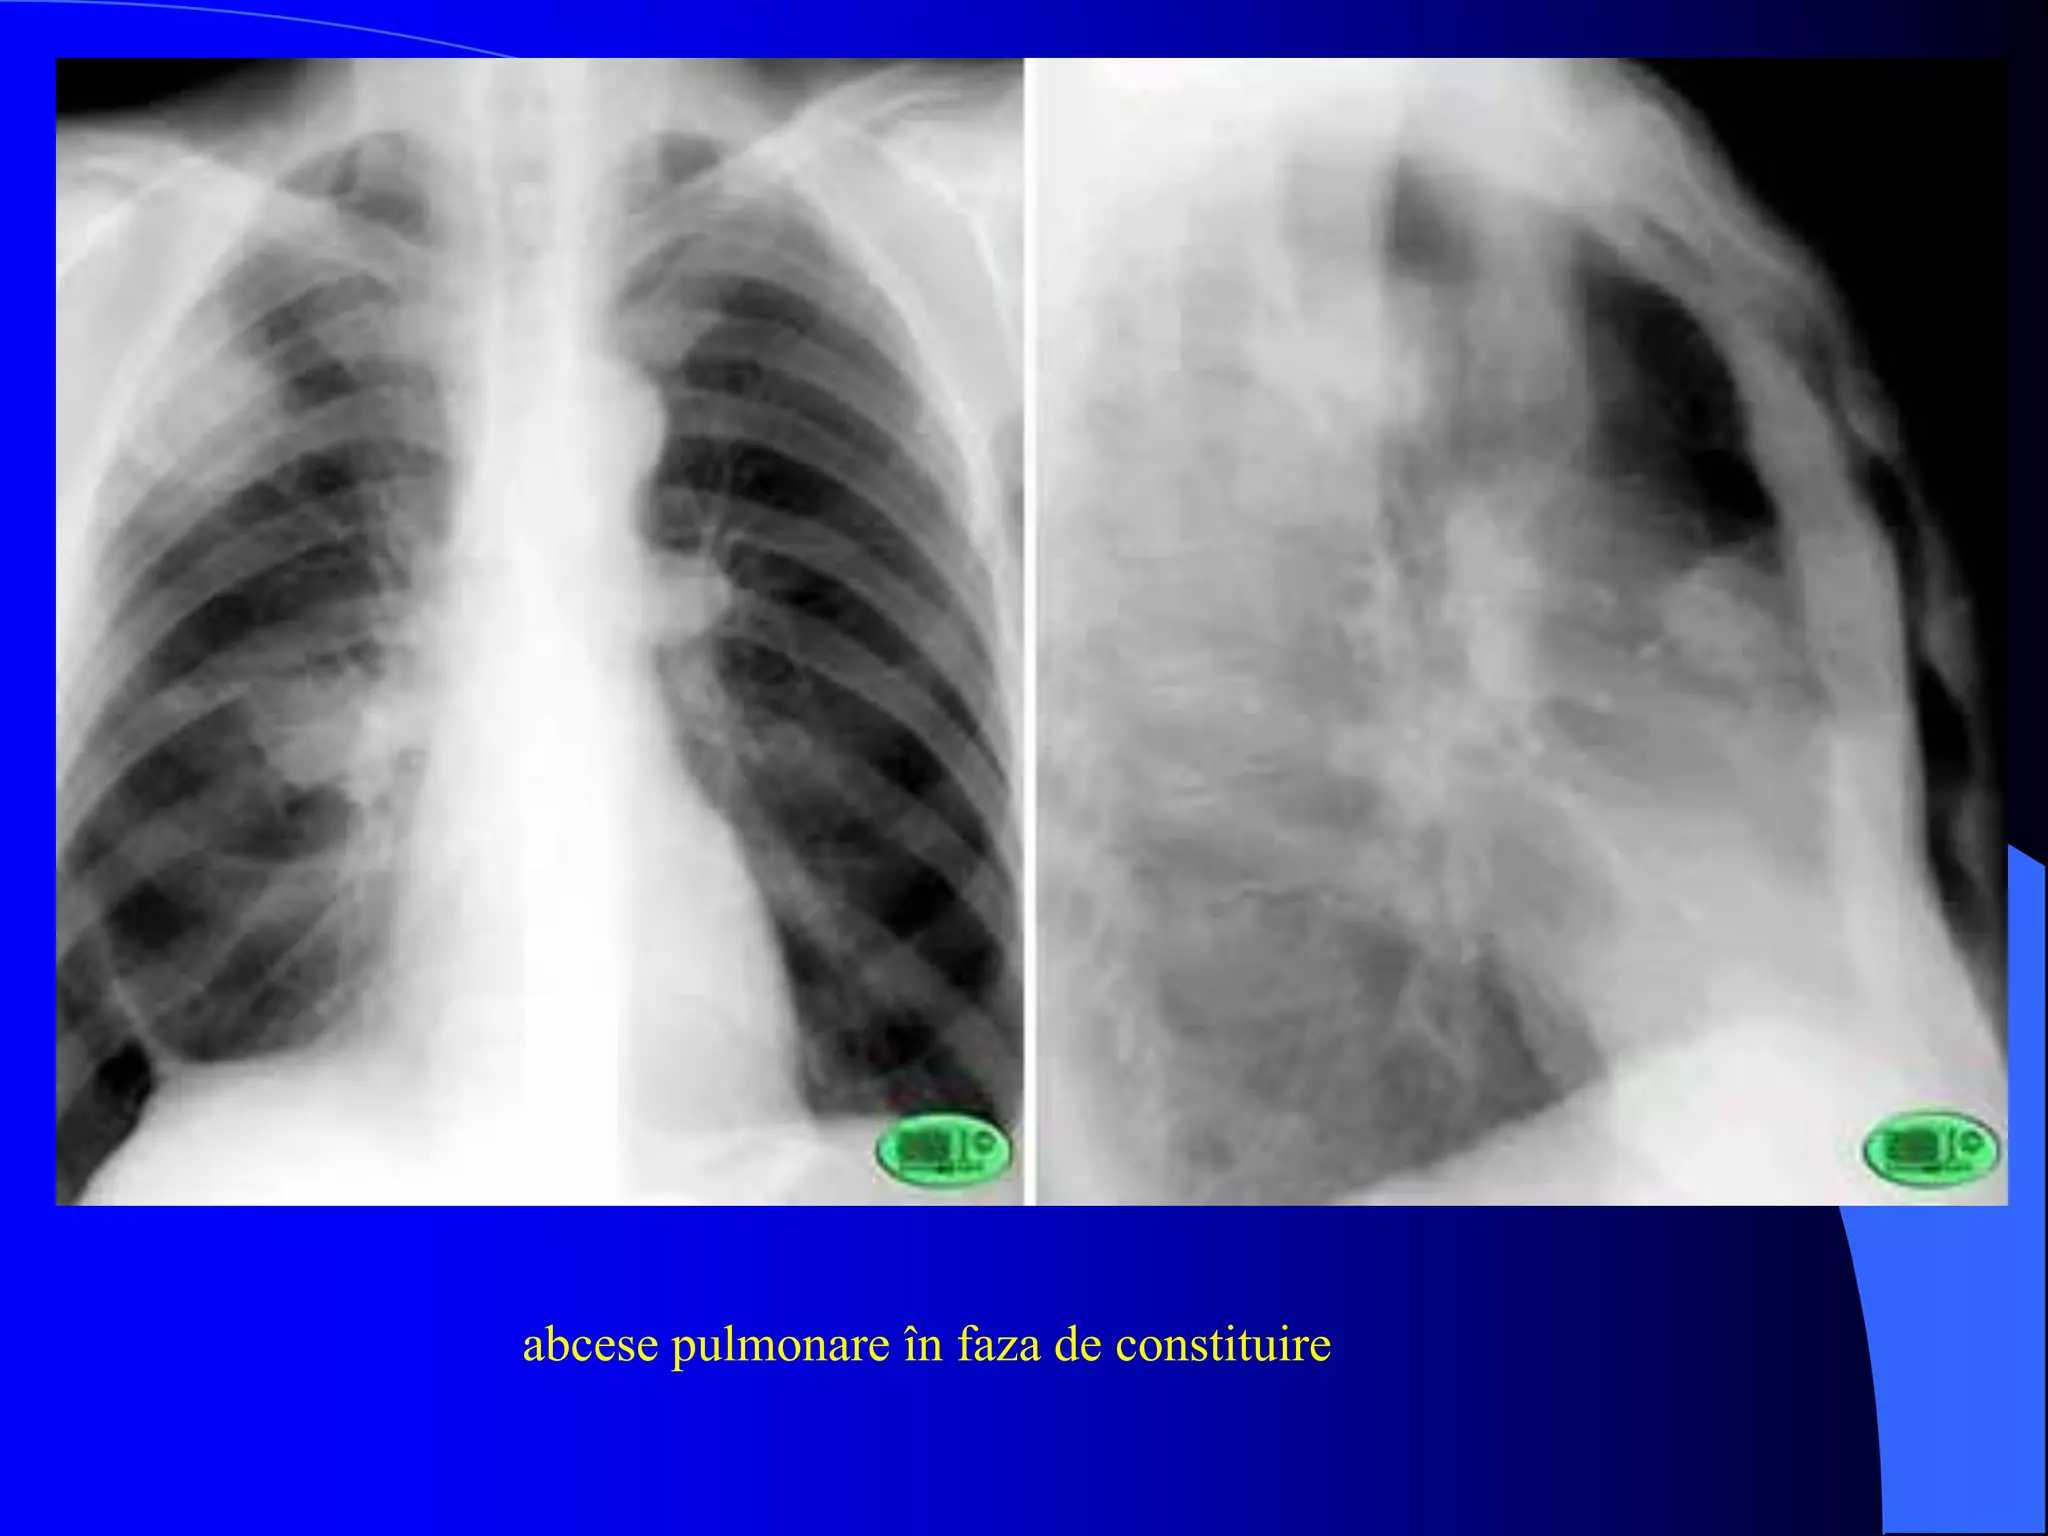

abcese pulmonare în faza de constituire

- acelaşi caz prezentat anterior; imagine hidro-aerică localizată în lobul superior

drept

- aspect dupa vomica (săgeată)

în interiorul ariei de condensare pulmonară se observă două imagini hidro-

aerice suprapuse (aspect în gură de cuptor)